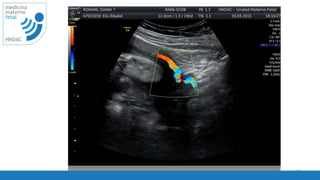

ISUOG - Guidelines 2013

tecnica

2-3T

• localizar la arteria uterina en

el cuadrante inferior

• localizar la arteria ilica

• localizar el cruce de la arteria

uterina e iliaca

• tomar la muestra 1 cm por

encima del cruce